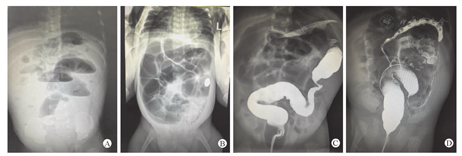

保守治疗组经过急性期治疗后,开奶不久出现喂养不耐受,如胃潴留、呕吐、腹胀等症状,排便次数及量减少。本组中有8例患儿肠狭窄出现在近端回肠,距离回盲部约50~60 cm,狭窄位置偏高(图1A),临床表现以呕吐腹胀为主,呕吐发生率为87.5%,腹胀发生率为75%,腹部X线立位片提示肠梗阻。59例患儿肠狭窄位置以远端回肠和结肠为主,远端回肠的肠狭窄距离回盲部约2~12 cm,临床表现以腹胀为主,腹胀发生率为100%,腹部X线立位片提示不同程度的肠胀气或低位肠梗阻(图1B)。对22例患儿行结肠造影,其中16例发现典型结肠狭窄(图1C),6例未见结肠狭窄,造影剂无法顺利通过回盲部,但可见明显扩张的近端小肠。手术造瘘组患儿经过肠造瘘后,近端肠管未发生狭窄,肠狭窄发生在造瘘口远端,患儿并无肠狭窄相关临床症状,只在肠造瘘回纳时常规探查远端肠管发现肠狭窄。14例患儿行结肠造影,检查结果均显示结肠狭窄(图1D)。

保守治疗组患儿肠狭窄出现的时间范围在13~86 d,平均30.5 d。手术造瘘组患儿在二次手术时常规探查远端肠管发现有肠狭窄,肠狭窄出现的时间无法确定。关于肠狭窄的部位,107例患儿共有185处狭窄,53例患儿伴多发肠狭窄,其中9处狭窄出现在近端回肠,42处出现在远端回肠(回盲部),63处出现在升结肠,41处出现在横结肠(脾曲),19处出现在降结肠,11处出现在乙状结肠。保守治疗组患儿肠狭窄部位以远端回肠(回盲部)、升结肠和横结肠(脾曲)为主,手术造瘘组以升结肠和横结肠(脾曲)为主。整组结肠狭窄所占比例为72.4%(134/185),其中保守治疗组为67.5%(79/117),手术造瘘组为80.9%(55/68)。

NEC后肠狭窄发生的时间因患儿初始病情的严重程度及发病部位不同而有差异,在急性期缓解后的前3个月是肠狭窄发展的关键时期[3]。Heida等[3]研究发现患儿经过保守治疗后出现肠狭窄症状的时间为16~91 d。Goettler等[9]报道了1例于NEC后11年继发了肠狭窄的病例。本研究中67例保守治疗患儿,肠狭窄发生的时间为13~86 d,平均30.5 d。文献报道NEC后肠狭窄的部位以结肠为主,Gaudin等[4]研究报道80%以上的肠狭窄发生在结肠。Heida等[3]发现经过保守治疗后肠狭窄的部位主要为横结肠和降结肠,经过手术治疗后的部位主要为升结肠。肠狭窄以结肠和末端回肠为主,可能与回盲部的解剖位置及功能特殊性相关。左半结肠的血流低于其他肠段,结肠的活动也伴随减少,尤其是脾区,是肠系膜上和肠系膜下动脉供血的终端,对缺血的敏感性相应增加,所以是狭窄的常见部位。本研究保守治疗组患儿肠狭窄部位以远端回肠(回盲部)、升结肠和横结肠(脾曲)为主,手术造瘘组以升结肠和横结肠(脾曲)为主,整组结肠狭窄所占比例为72.4%(134/185),其中保守治疗组为67.5%(79/117),手术造瘘组为80.9%(55/68),两组之间的差异考虑与手术造瘘组切除病变坏死的小肠有关,切除了可能发展为肠狭窄的小肠,结肠狭窄比例增加。需要强调的是肠狭窄有很大的可能性是多发的,本研究中有53例患儿为多发肠狭窄,故术中需探查所有肠段以防多发肠狭窄。

NEC后肠狭窄患儿的临床表现为反复出现喂养不耐受,如胃潴留、呕吐、腹胀、便秘等。肠狭窄严重程度不同或梗阻位置不同,其症状严重程度和发生时间均有不同,肠狭窄严重或梗阻位置较高的患儿,症状出现的早,反之症状出现较晚。对于肠造瘘的患儿,狭窄段往往在造瘘远端,可无明显的临床症状。NEC后肠狭窄的辅助检查,腹部立位X线平片为首选,多数可表现为低位肠梗阻或肠胀气。结肠造影检查对于结肠狭窄有很高的特异性[10]。本研究中36例患儿接受结肠造影检查,有30例提示结肠狭窄,其中19例提示降结肠狭窄,11例提示乙状结肠狭窄,与术中证实狭窄位置一致。对于结肠造影检查未见肠狭窄的患儿,要注意近端小肠的扩张情况,结合临床症状及病史予以甄别,必要时行全消化道造影。对于NEC病史明确,临床症状典型,腹部立位X线平片提示肠梗阻的患儿,就有手术探查指征。